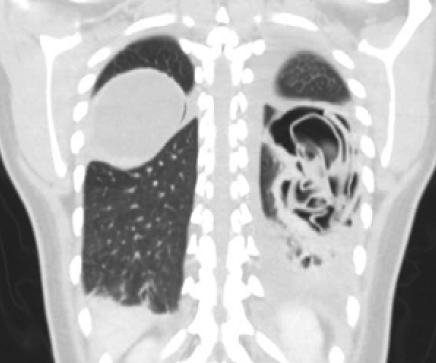

Guillermo Rencoret Palma, Marcelo Vivanco Lacalle, Felipe Andrés Castillo Henriquez, Giancarlo Schippacasse, Xabier De Aretxabala Urquiza, Victor Bianchi, Juan Hepp, Horacio Rios